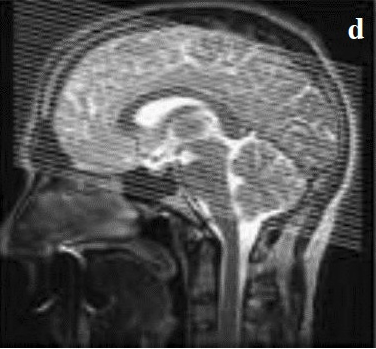

AXIAL FIELD MAP

Angulate parallel to AC-PC line, then tilt 15 degrees toward TOP of head. Send source images to PACS